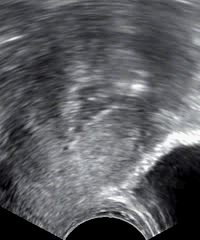

In postmenopausal bleeding, guidelines from the United States consider transvaginal ultrasonography to be an appropriate first-line procedure to identify which women are at higher risk of endometrial cancer. A cut-off threshold of 3 mm or less of endometrial thickness should be used for in women with postmenopausal bleeding in the following cases:

- Not having used hormone replacement therapy for a year or more

- Usage of continuous hormone replacement therapy consisting of both an estrogen and a progestagen

A cut-off threshold of 5 mm or less should be used for women on sequential hormone replacement therapy consisting both of an estrogen and a progestagen.[4]

It the endometrial thickness equals the cut-off threshold or is thinner, and the ultrasonography is otherwise reassuring, no further action need be taken. Further investigations should be carried out if symptoms recur.[4]

If the ultrasonography is not reassuring, hysteroscopy and endometrial biopsy should be performed. The biopsy may be obtained either by curettage at the same time as inpatient or outpatient hysteroscopy, or by using an endometrium sampling device such as a pipelle which can practically be done directly after the ultrasonography.[4]